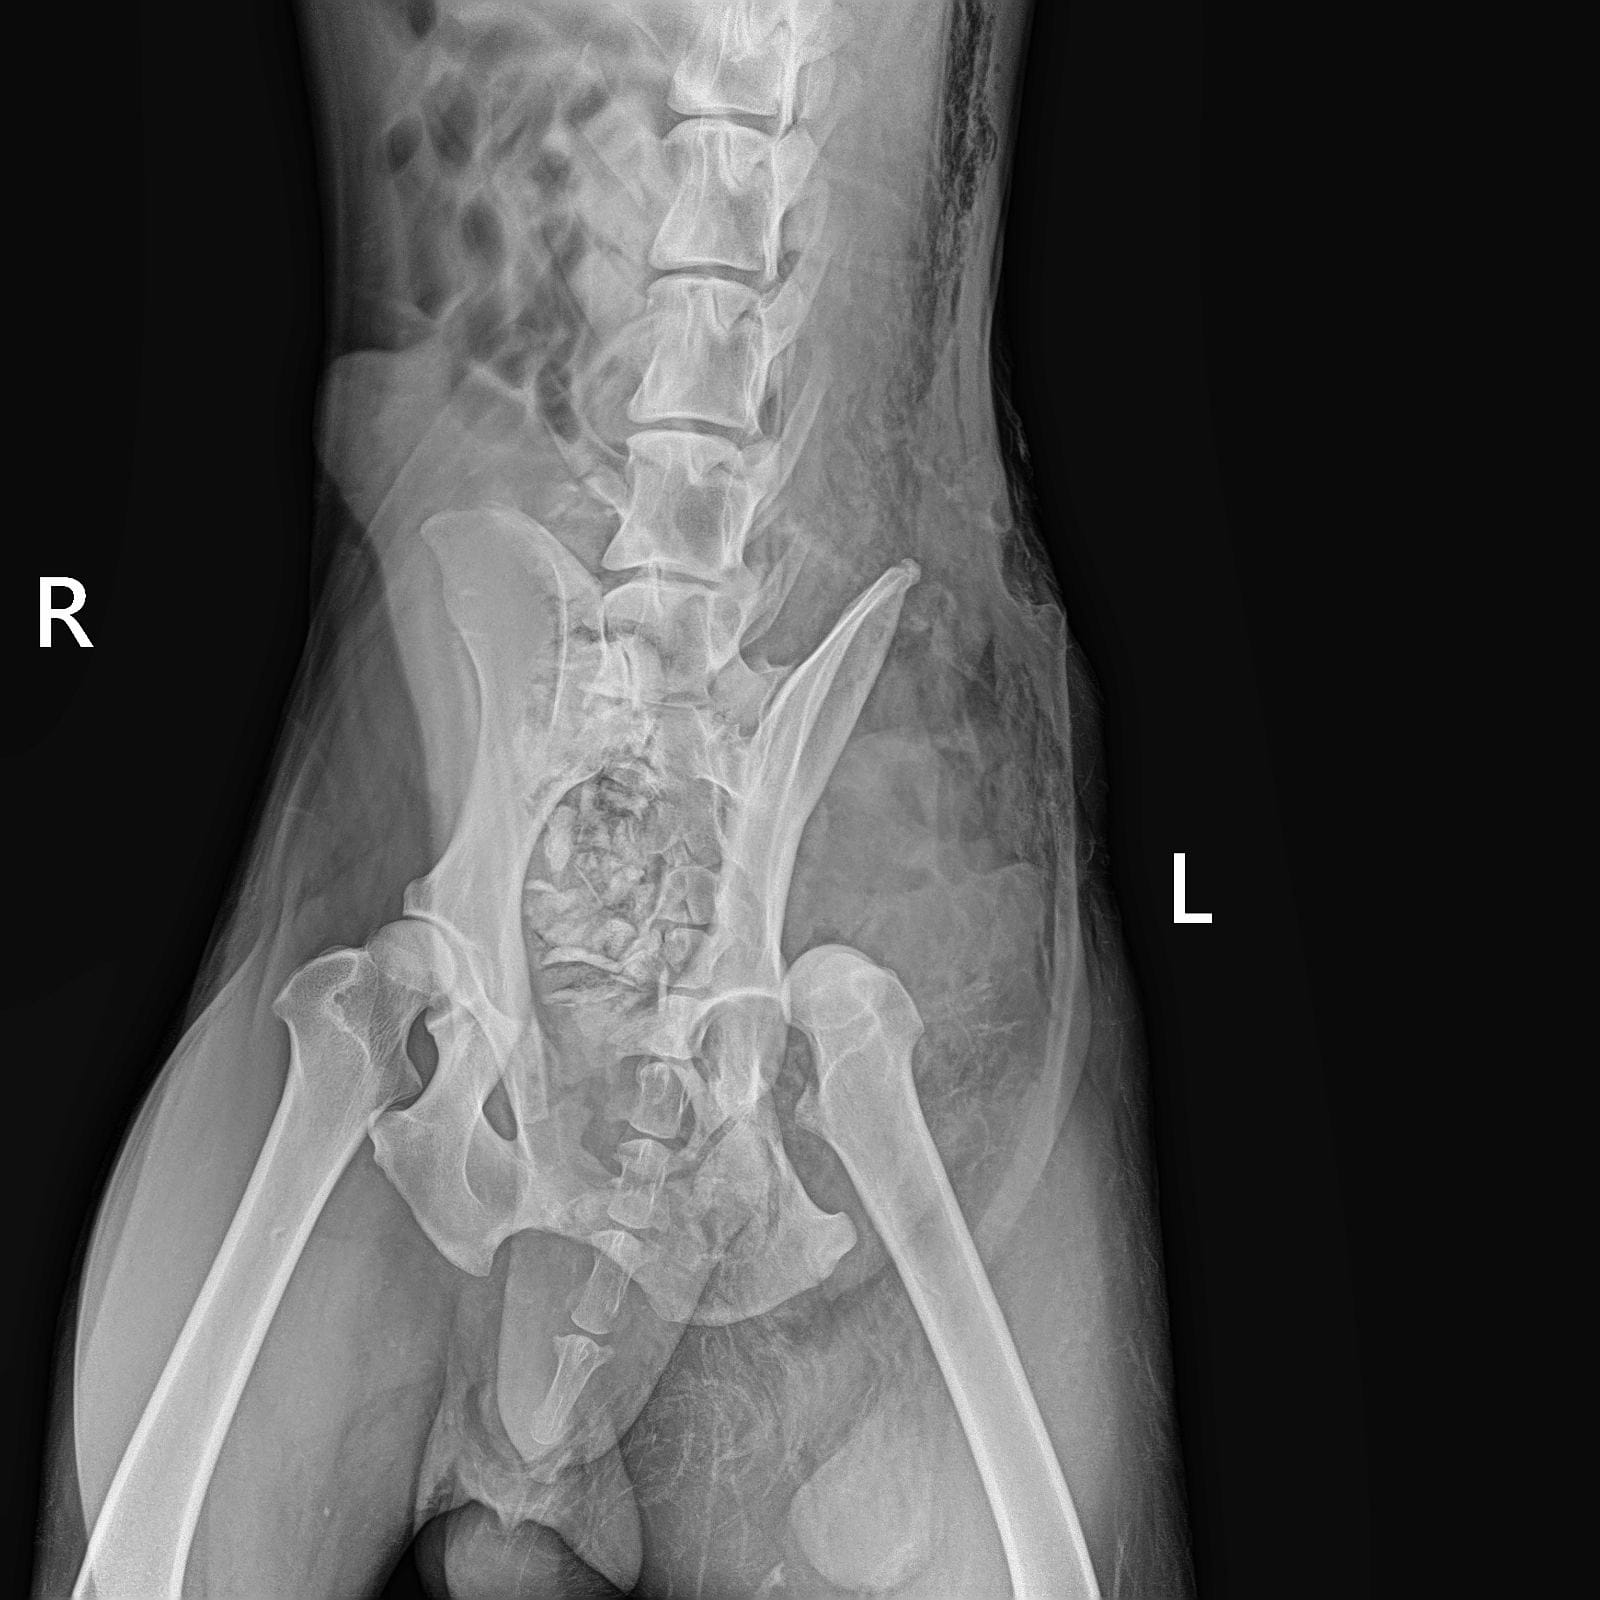

Обследования из клиники Рекс

Выписка из Зоозащиты